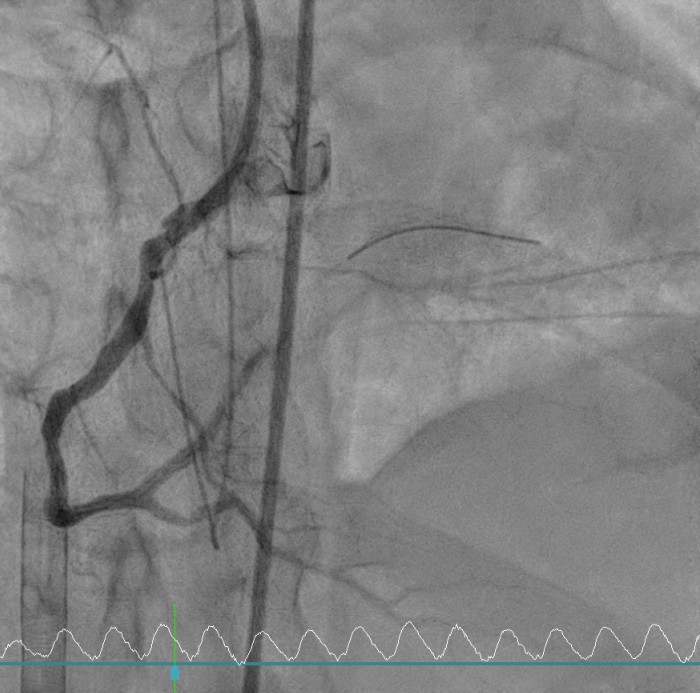

Relevant Catheterization Findings

Coronary angiography revealed critical left main and triple-vessel coronary artery disease. The right coronary artery and posterolateral branch were totally occluded, serving as infarct-related lesions. TIMI flow improved from 0 to 3 after deployment of two drug-eluting stents in the RCA and RCA-PL. Residual severe disease in the left main, LAD, and LCX was reserved for staged PCI. Periprocedural VT was defibrillated twice (200 J) under VA-ECMO and IABP support.

Primary Intervention (Feb 28): During extracorporeal cardiopulmonary resuscitation, two drug-eluting stents were implanted in the right coronary artery and posterolateral branch under VA-ECMO and IABP support. Ventricular tachycardia during PCI was successfully defibrillated, and targeted temperature management was initiated.